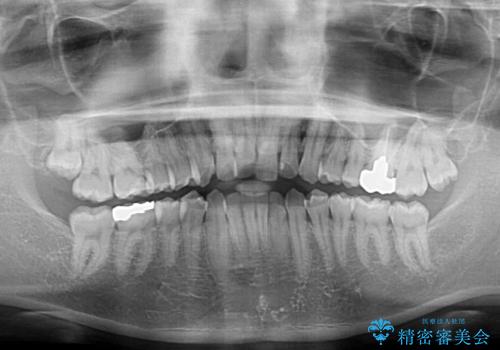

- 上下前歯のデコボコを気にして来院された患者様です。

マウスピース矯正でもワイヤー矯正でも対応可能でしたが、インビザラインによる自己管理が煩わしいとのことで、ワイヤー装置にて矯正治療を行うこととしました。

口元はやや突出感がありましたが抜歯矯正をするほどではないため、舌突出癖を改善するトレーニングをしっかりと行っていただき、現在よりも唇が閉じやすい位置に仕上げていくこととしました。

下顎前歯が思っていた以上に動きが悪く、想定よりも期間がかかってしまいました。

矯正治療後には気になっていた銀歯をセラミックで自然な色に仕上げました。